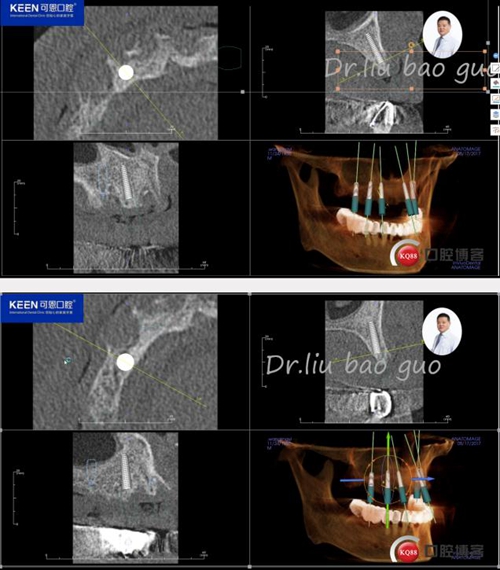

手術前種植軟件設計方案

3.jpg

4.jpg

5.jpg

6.jpg

數字化種植導板設計及制作

7.jpg

8.jpg

9.jpg